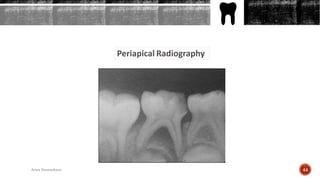

INTRAORAL RADIOGRAPHY

Periapical Radiography

Periapical radiographs should show the crown of the tooth

and at least 3 mm beyond the apex of the tooth.

To achieve this coverage, one can use either: